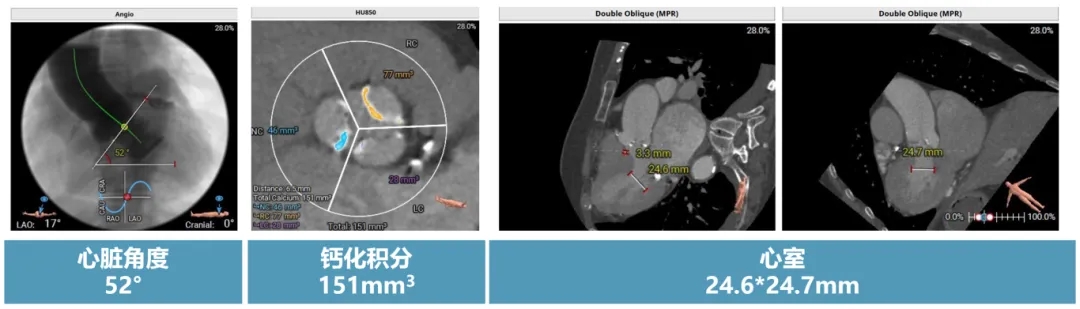

主动脉CT术前评估

三叶式主动脉瓣,瓣叶钙化。瓣环径 22.2mm,LVOT 21.3mm,瓣上无明显限制,窦部空间可,冠脉高度可。

CT动图